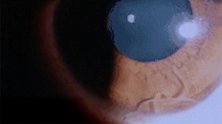

关于“干眼症”的视频